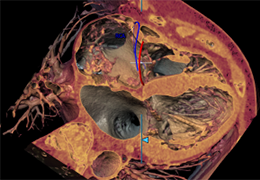

View X-Ray CT & MRI Scans Fast and Easily

Designed for surgeons, Pro Surgical 3D makes it easy to view patient scans quickly. Pro Surgical 3D facilitates the optimal 3D treatment and assessment workflows based on X-ray CT and MRI scans – and best of all, it’s FREE!

Everyone – including surgeons, patients and their loved ones – benefits from being better informed by the wealth of information buried within CT and MRI scans. Pro Surgical 3D gives surgeons more information to develop optimal treatment plans for patients. It also helps patients and their support group better understand their medical condition and proposed treatment options.

Performs 3D reconstruction and volume rendering.

Multi-planar slicing.

Oblique slicing.

Axis-aligned cropping with context.